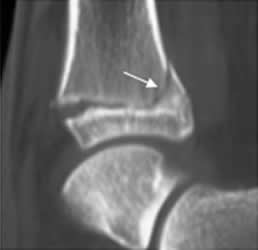

Fig 77. Salter tipo IV.

A: Rx AP y B: TAC reconstrucción sagital. Fracturas oblicuas con compromiso de las epífisis y metáfisis del tobillo y la rodilla.